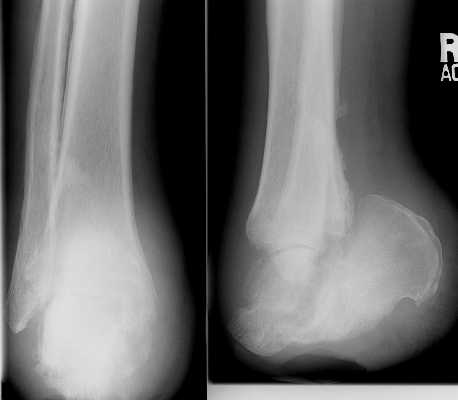

These images show an amputation through the calcaneal-cuboid and talo-navicular joints

(Chopart level).

Selected images of different patients showing the Chopart amputation.